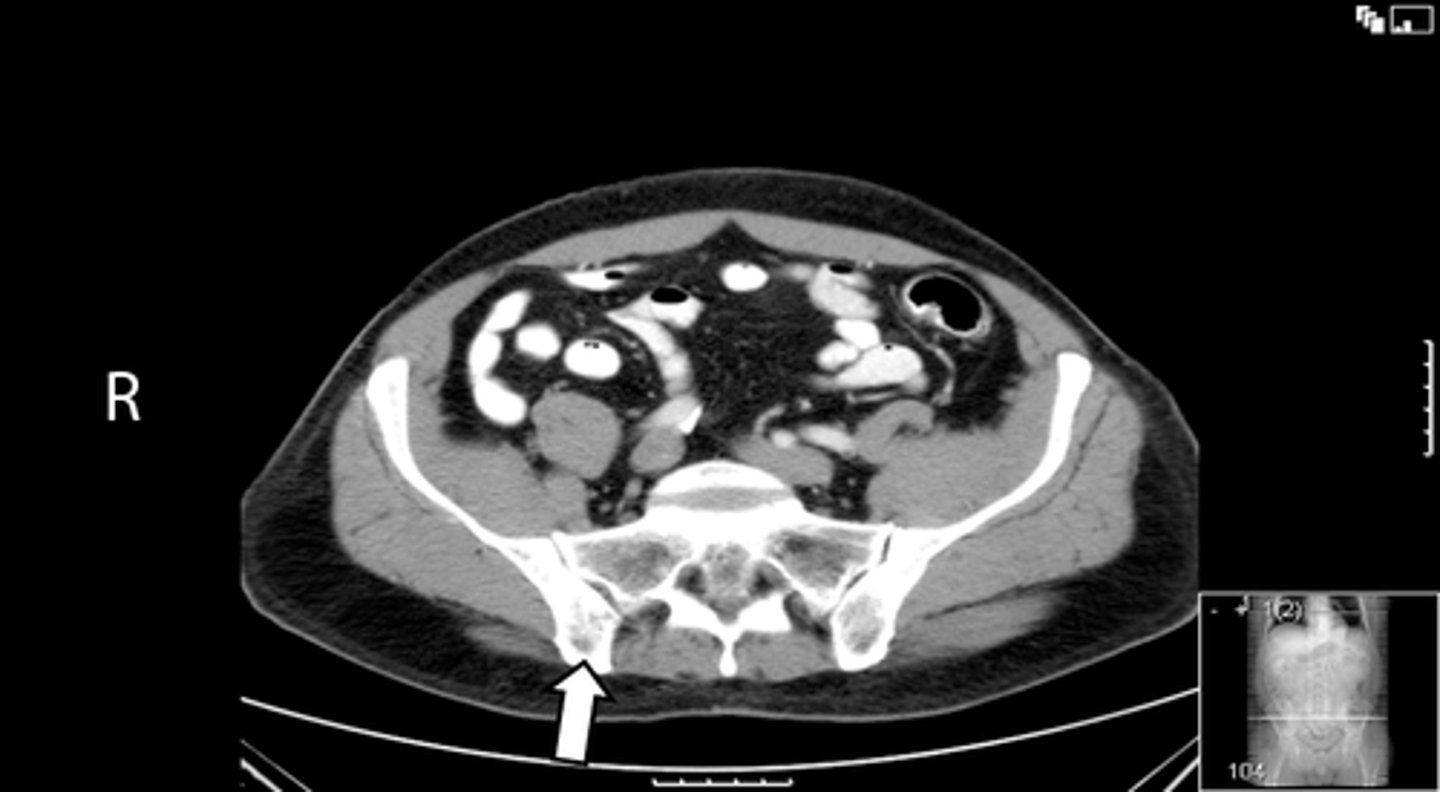

Axial bony pelvis CT

What is the image?

L ilium

What is indicated in the image?

L sacroiliac joint

R ilium

R sacroiliac joint

Sacrum

L acetabulum

L femoral head

L piriformis muscle

R femoral head

R piriformis muscle

R acetabulum (posterior part)